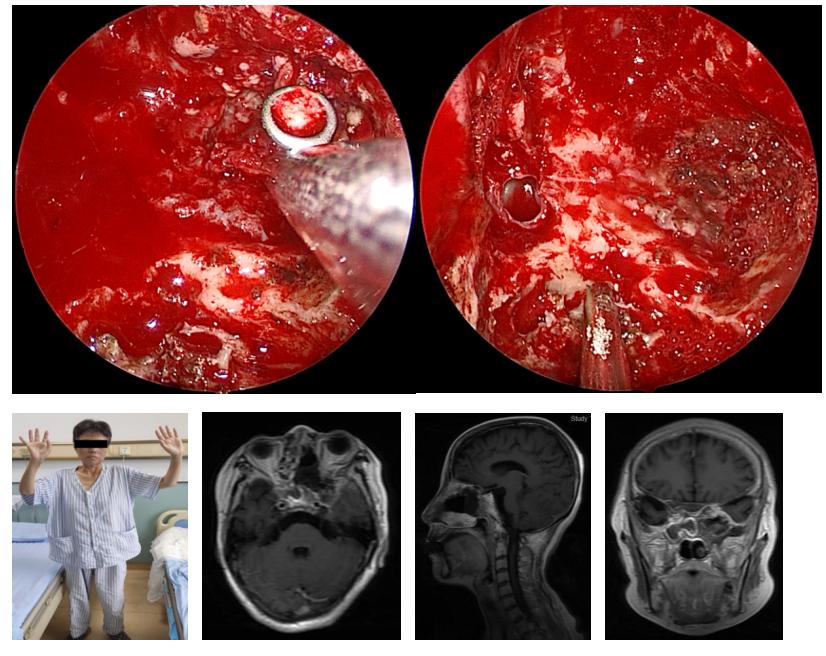

术前神经外科王宁教授团队与耳鼻喉科李慧军教授团队一同制定了周密的手术计划,手术如期顺利进行,先由耳鼻喉科王启威副主任医师内镜下行筛窦、上颌窦开放,并切除侵及相关区域病变。然后神经外科王宁教授及邵奇主治医生内镜下进行了侵及翼腭窝、蝶窦、海绵窦病变的切除。术后进行磁共振检查显示肿瘤全切,困扰折磨患者已久的典型三叉神经痛症状消失,恢复满意出院。

王宁教授介绍,复杂型颅内外沟通病变仍然是神经外科领域高难度的手术之一,它需要多学科协同合作,相互配合,才能顺利治愈疾病。通过内镜处理此类病变的优势在于其视角大,可以直观范围较大的病变;可以抵近观察,清晰地显示病变;经鼻处理某些位于颅底的病变,更直接、更安全。